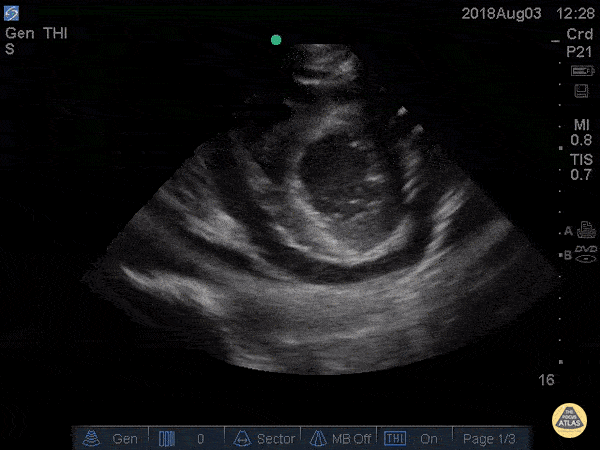

Pericardial Disease - Cardiac Tamponade Parasternal Short

41 yo M with history of stage 4 lung cancer presents with AMS and dyspnea, normotensive and tachycardic to 140s. Parasternal long view showed moderate pericardial effusion with RV collapse. With M mode we are able to see the RV wall collapse (top line) corresponds with the mitral valve opening i.e. it occurs during diastole. Even though the patient was normotensive he was taken to the OR for a pericardial window within the hour given this evidence of echocardiographic tamponade. Nathan Kabariti MS4, Dr. Charles Murchison, Dr. John Riggins, Dr. Donald Doukas - Kings County Emergency Medicine